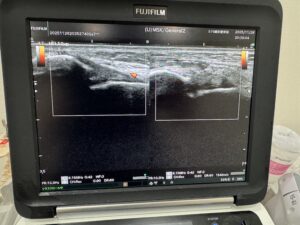

当院では急性期のケガについて、しっかりとエコー検査と、その他問診を行い

最短で復帰に向けてサポートさせて頂いております

今回は初めての捻挫でご来院された患者様でしたが、骨折等は否定的で

足首の靭帯損傷等によるものと判断し、荷重ができるギプス固定をさせて頂きました。